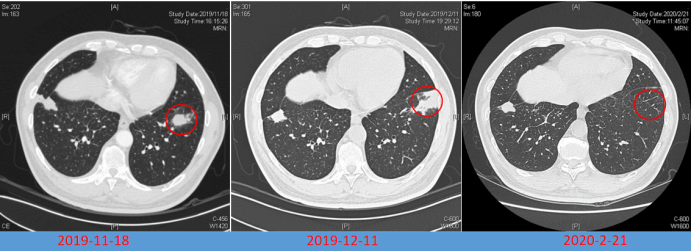

病例5:男性,64岁,主因“咳嗽、咳痰伴双肺多发阴影3个月,咯血1天”于2019年11月14日入院。7月23日因多发肺部结节影,诊断肺结核,予四联抗结核治疗。10月29日因糖尿病酮症酸中毒于我院普内科住院,期间查胸部CT提示双侧胸腔积液,心影增大,考虑合并心功能不全,对症治疗后好转出院。11月13日患者突发咯血,20~30口,鲜血,收入呼吸内科病房。借助导航支气管镜获取组织标本,经冷冻肺活检发现组织内有大量菌丝,同时送检的mNGS检测到毛霉序列,通过组织病理联合组织mNGS,真正意义上实现了毛霉病的确诊。因患者拒绝全身用药,遂实施局部用药方案。在导航支气管镜与超声技术的辅助下精准定位病灶后,对其进行两性霉素B的精准局部灌注治疗。经过两次该治疗,病灶成功消失(图5)

图片

图5  病例5治疗前后胸部CT比较